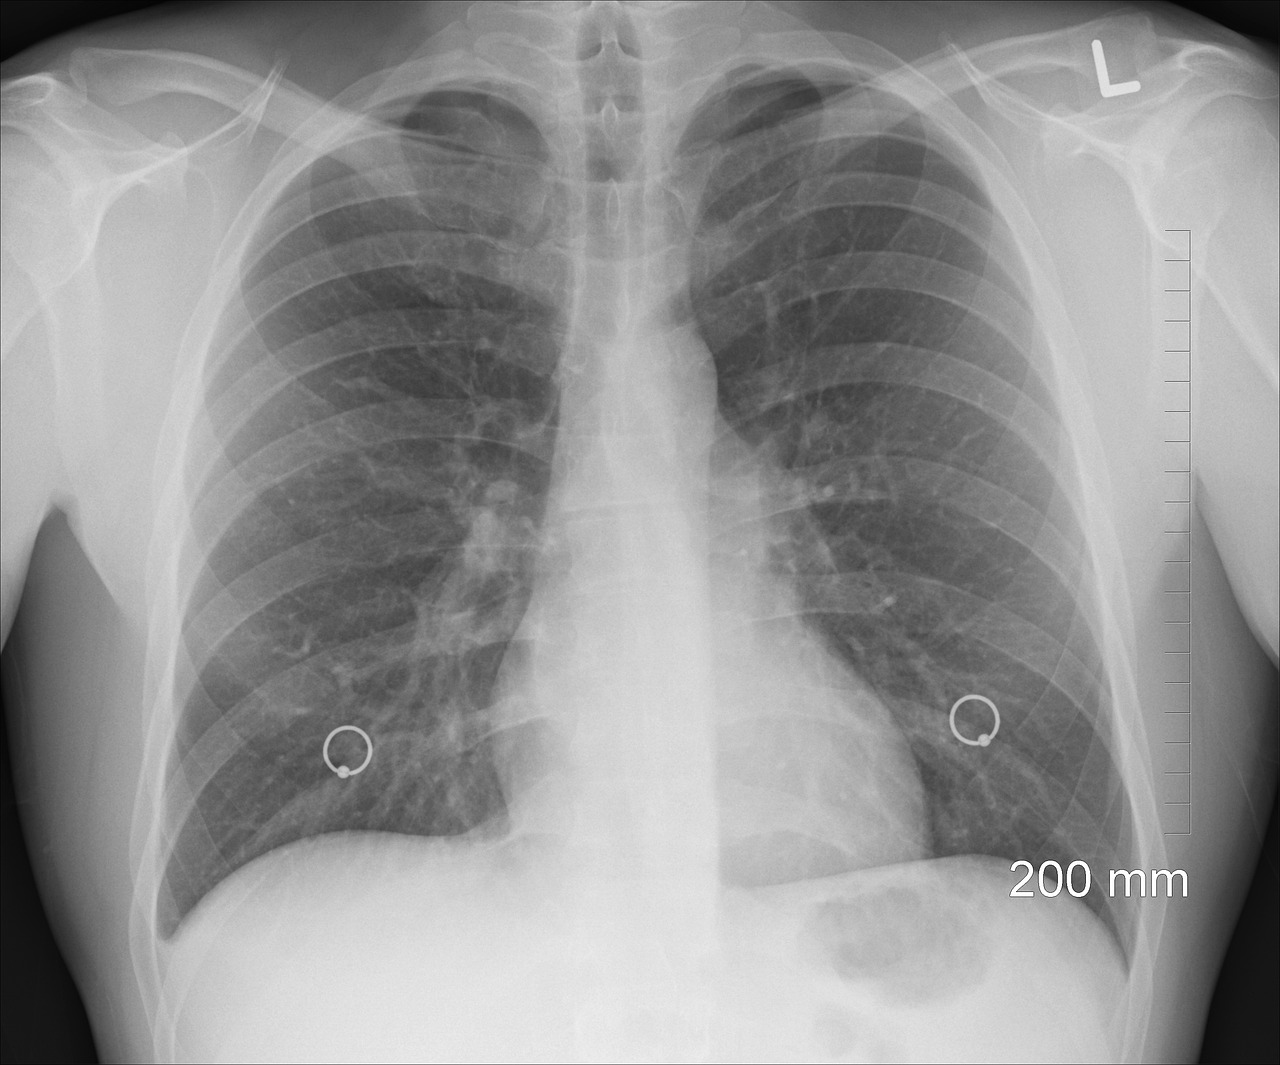

La nouvelle définition du SDRA est présentée dans le tableau 1 et les mises à jour de la définition de Berlin dans le tableau 2. La figure 1 représente une illustration de la nouvelle définition du SDRA.

Radiographie thoracique Les opacités bilatérales non expliquées par un épanchement pleural, une atélectasie ou une masse pulmonaire à la radiographie thoracique restent un critère obligatoire. Même si la reproductibilité de l'interprétation entre chaque lecteur est faible (13), elle reste l'imagerie la plus couramment utilisée chez les patients graves. L'échographie thoracique est retenue comme une méthode diagnostique supplémentaire pour identifier les condensations bilatérales d'origine non cardiogénique, en particulier lorsque la radiographie et le scanner thoracique ne sont pas disponibles (14-16). Cet examen est considéré comme fiable avec un opérateur formé.

Figure 1 : Cas illustratifs de patients avec les descriptions, l'imagerie pulmonaire et les données d'oxygénation pour les 3 catégories de SDRA de la nouvelle définition : SDRA intubé (haut), SDRA non intubé (milieu), SDRA dans un pays à ressources sanitaires limitées (bas). Le patient dans le pays à ressources sanitaires limitées peut être identifié à l'aide d'une échographie, radiographie ou scanner. De plus, le seul avec un SDRA intubé répond aux critères du SDRA de la définition de Berlin. P/F = PaO2:FiO2 ; S/F=SpO2:FiO2 ; SpO2 = saturation en oxygène mesurée par saturomètre.